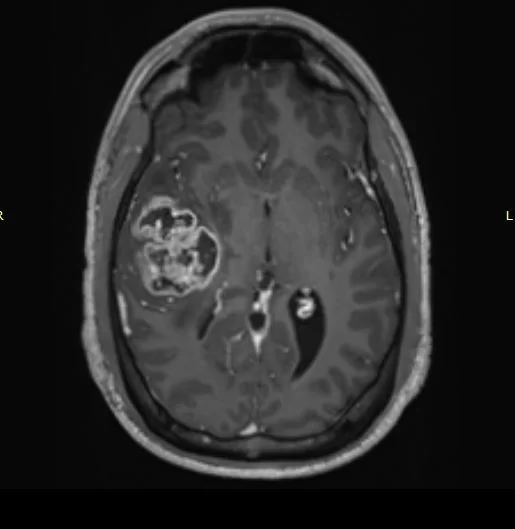

H Μαγνητική Τομογραφία εγκεφάλου ανέδειξε εκτεταμένη χωροκατακτητική εξεργασία δεξιά κροταφικά με πίεση επί του σύστοιχου κροταφικού κέρατος και σημαντικό περιεστιακό οίδημα.

Αρχικά διενεργήθηκε ενδελεχής έλεγχος στα πλαίσια προετοιμασίας της χειρουργικής επέμβασης (οπτικά πεδία: φυσιολογικά), λειτουργική μαγνητική τομογραφία (fMRI) και δεσμιδογραφία).

Προεγχειρητικά ο όγκος και η σχέση του με τις σημαντικές ανατομικές δομές και λειτουργίες μελετήθηκε με τη βοήθεια της λειτουργικής μαγνητικής και της μαγνητικής δεσμιδογραφίας. Με απλά λόγια, αυτές οι εξετάσεις μας έδειξαν πόσο μακριά είναι ο όγκος από όλα εκείνα τα στοιχεία που θέλουμε να προφυλάξουμε.